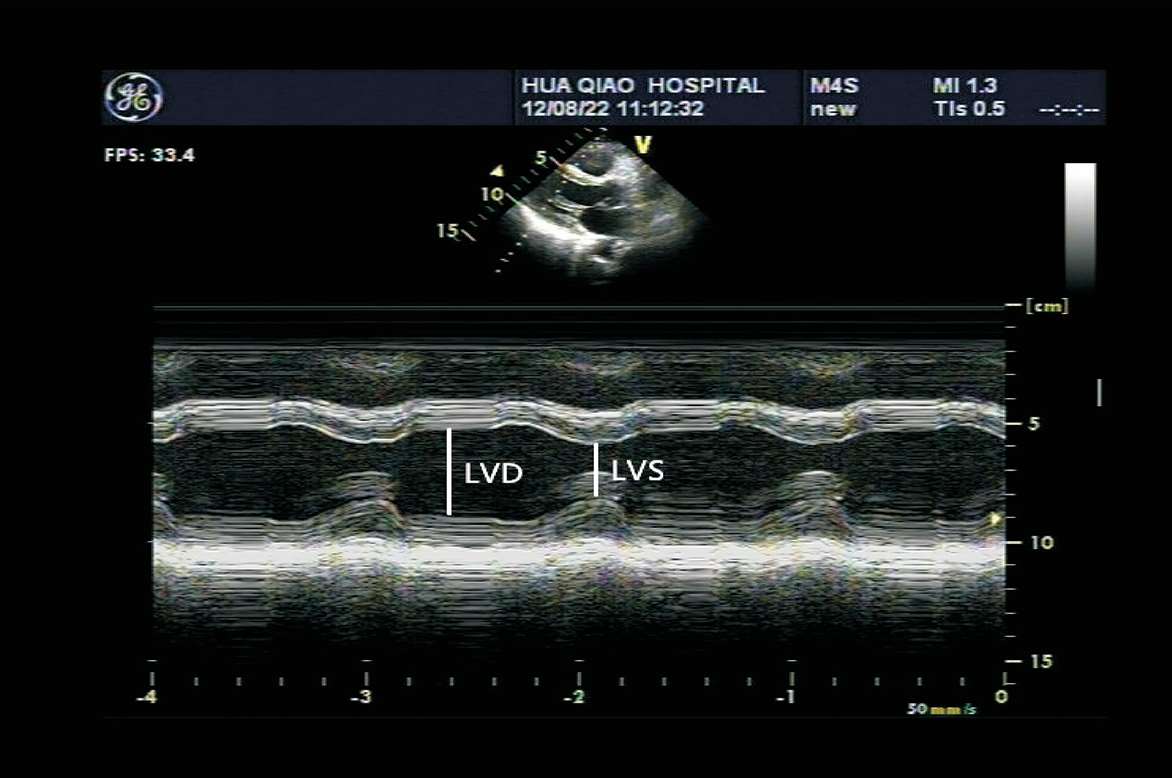

(1)M型超声心动图,适用于左心室无节段性运动异常者。取标准胸骨旁左心室长轴切面,取样线置于二尖瓣腱索水平,测量左心室舒张末期内径(LVD)与收缩末期内径(LVS),根据测量内径推算左心室舒张末期及收缩末期的容量,再根据左心室舒张末期容量及收缩末期容量的变化求出心输出量(见图1-36)。

图1-36 左心室波群